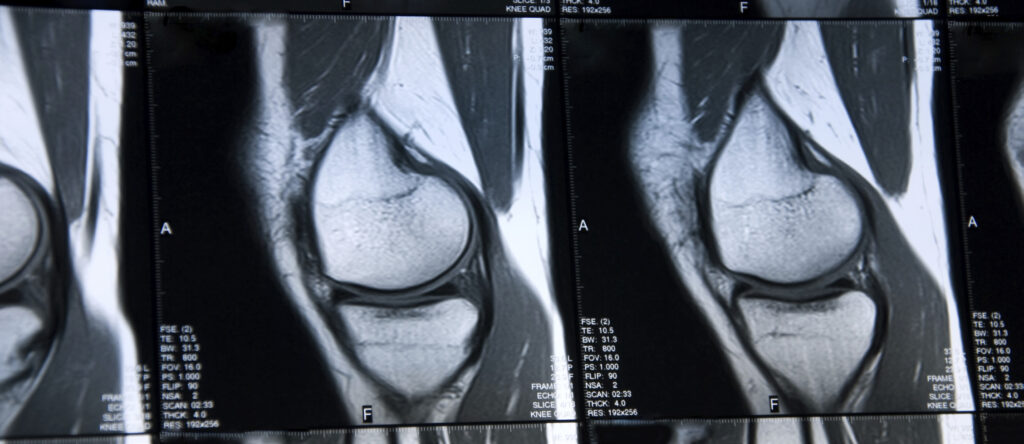

Medical Imaging of Osteoarthritis of the Knee in Clinical Trials